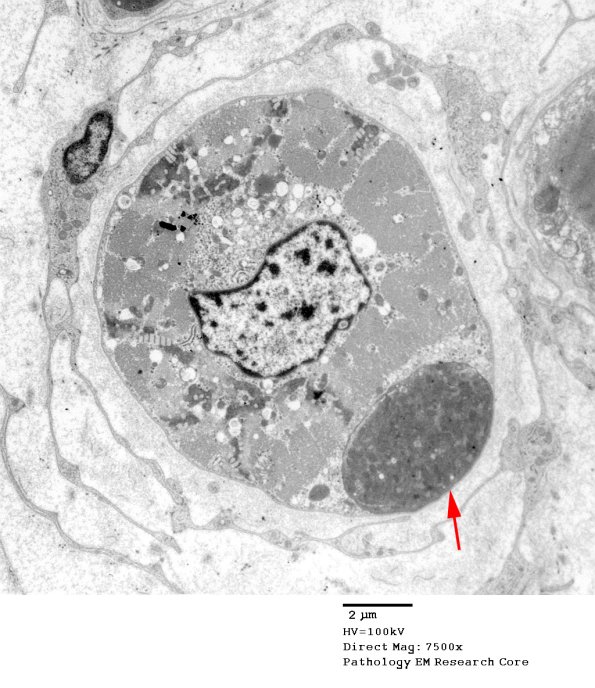

3B1A-C This unusual axon (arrow, 3B1A) is osmiophilic with densely compacted mitochondria. (electron micrographs)